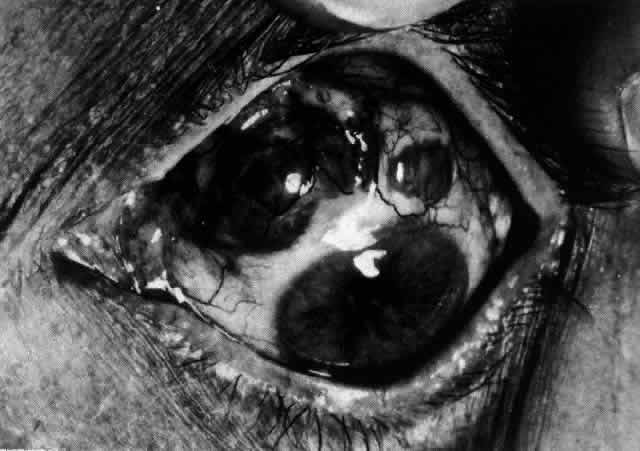

The angiogram is similar to that of diffuse anterior scleritis (i.e., there is a rapid filling pattern and deep scleral leakage of dye).26 Necrotizing Anterior Scleritis with Inflammation Patients with necrotizing anterior scleritis with inflammation not only suffer extremes of discomfort but are in serious danger of losing an eye. Therefore, it is of great importance that the condition be detected early and treated adequately. (It is of equal importance that those varieties of scleral inflammation that are not destructive to the eye should not be treated with drugs that are themselves dangerous.) Accurate diagnosis is the key. Necrotizing scleritis accompanied by inflammation is always painful, waking the patient at night, increasing in intensity day by day, and leading to severe distress. The sclera is swollen, and the overlying inflammation is localized to the center of a lesion or to either end of an extending lesion (Fig. 37; Color Plate 1D). After inflammation, the sclera becomes transparent so that the underlying choroidal pigment becomes visible when viewed in daylight (Fig. 38). These areas may be invisible with the slit lamp. The area of inflammation extends outward around the globe from the original site of inflammation, often joining with other areas of scleritis that have subsequently appeared. If the inflammation is not suppressed, the process will progress around the globe until the whole anterior segment is involved (Fig. 39).

The characteristic features of necrotizing scleritis on fluorescein angiography are hypoperfusion and, eventually, nonperfusion of the vascular networks (Figs. 40 through 43).26 The initial changes are on the venous side of the capillary network; the transit time of the dye increases even if the eye is red and congested. If the disease process persists or has been present for a long time, thrombosis and permanent vaso-occlusive changes occur. These vessels (or the occluded capillary network) are bypassed by the opening of anastomotic channels. New vessels in a granuloma give rise to deep intrascleral leakage of dye (see Fig. 43). Conjunctival and episcleral involvement by the destructive change is late but is always preceded by vaso-occlusive changes that can sometimes be detected with use of the red-free light on the slit lamp (Figs. 44 and 45).